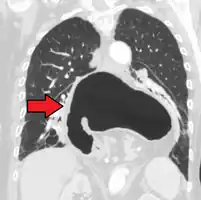

-

This hiatal hernia is mainly identified by an air-fluid level (labeled with arrows). -